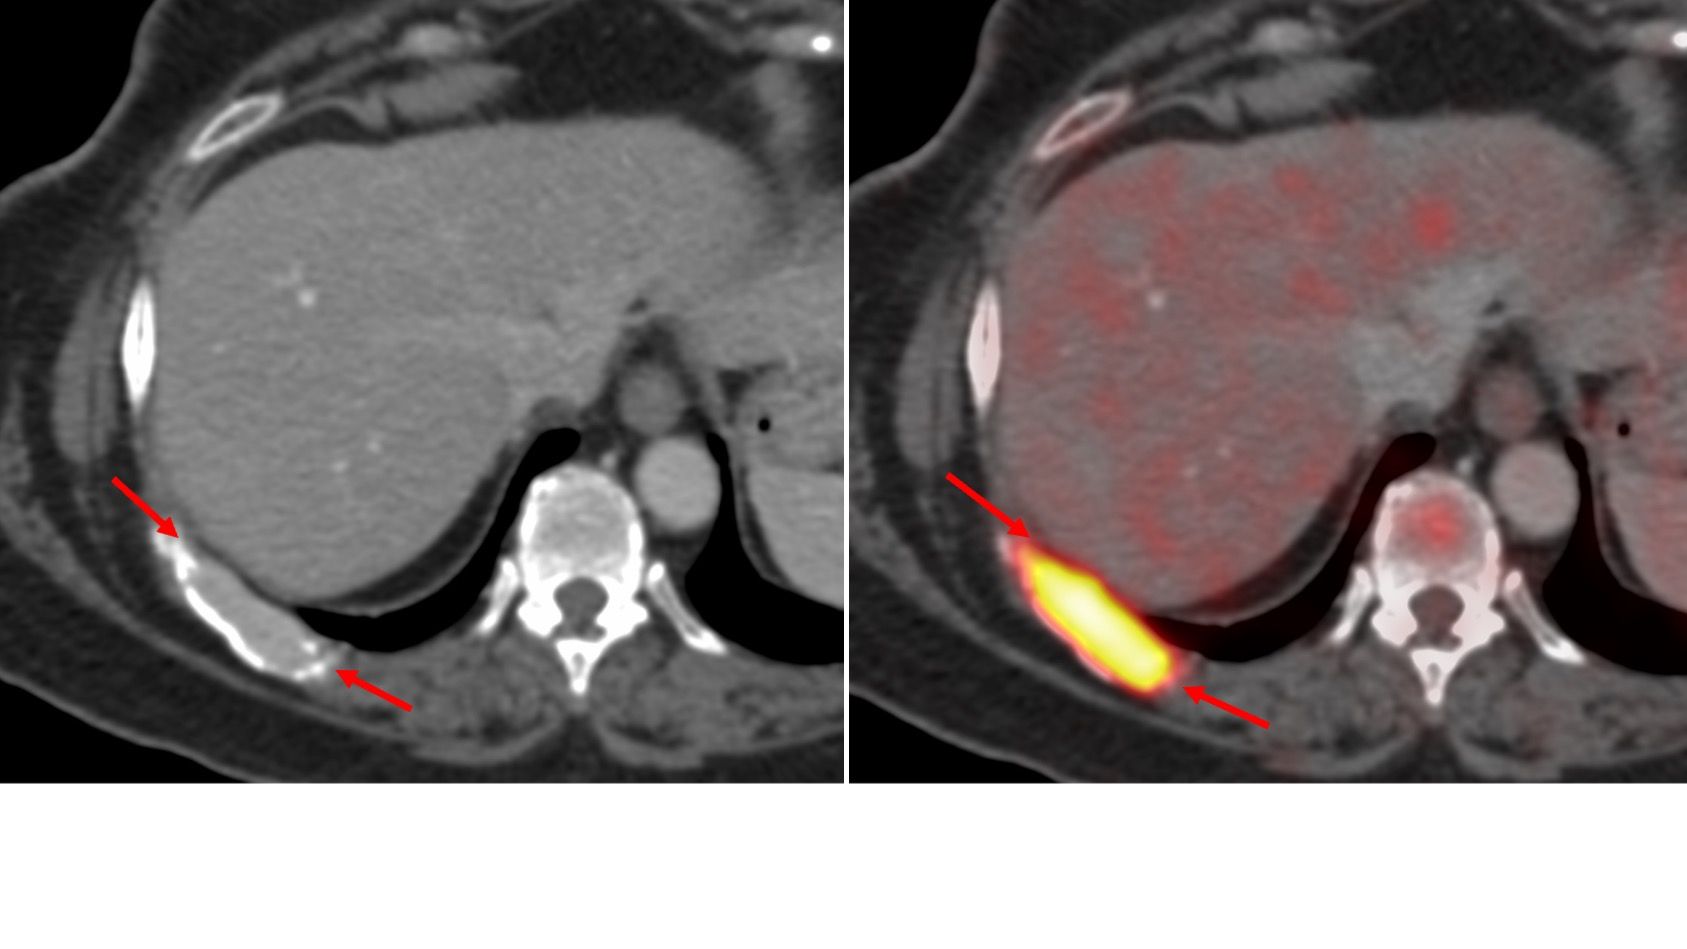

Case 111: Retrocrural Node Biopsy

Bhavin Jankharia - 05 December 2022